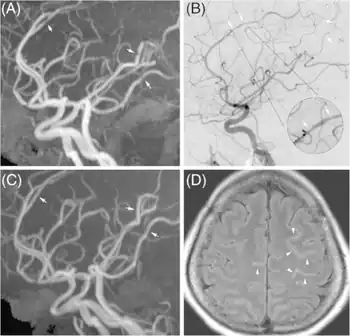

Significant beading of all intracranial arteries, best demonstrated in the anterior cerebral arties due to RCVS.

Reversible cerebral vasoconstriction syndrome a) Multifocal vasoconstriction b) anterior, middle, and posterior cerebral arteries c)follow-up indicated significant interval resolution of lesion d) linear hyperintensity lesions in the sulci of frontal lobes

RCVS is diagnosed by detecting diffuse reversible cerebral vasoconstriction.[2] Catheter angiography is ideal, but computed tomography angiography and magnetic resonance angiography can identify about 70% of cases.[2] Multiple angiographies may be necessary.[2] Because other diseases (such as atherosclerosis) have similar angiographic presentations, it can only be conclusively diagnosed if vasoconstriction resolves within 12 weeks.[2]